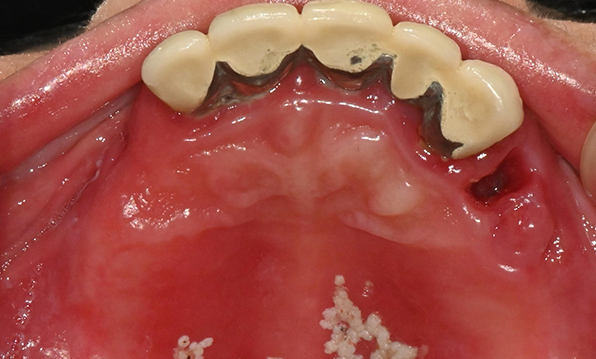

잇몸뼈가 얇은 상태

-

잇몸뼈 충분히 이식 후 임플란트 식립

성공을 위한 노하우, 잇몸뼈 재건 기술

전체 임플란트를 해야하는 환자들은

대부분 고령의 환자들로 오랜 틀니 사용

또는 노화로 인해 치조골이

거의 남아있지 않는 경우가 많습니다.

이 때, 치조골 이식을 병행하여 잇몸뼈 재건 후 안정적인 임플란트 식립을 하고 있습니다.